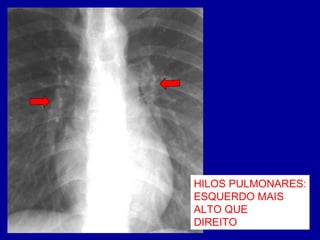

HILOS PULMONARES:

ESQUERDO MAIS

ALTO QUE

DIREITO